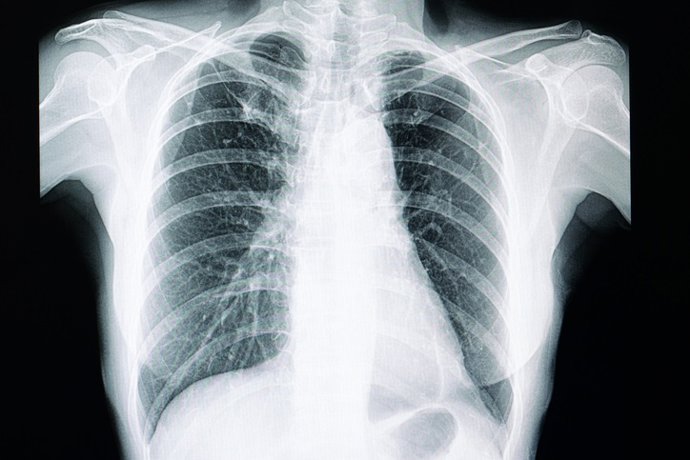

Archivo - Pulmones, radiografía de tórax

Archivo - Pulmones, radiografía de tórax - GETTY IMAGES/ISTOCKPHOTO / - Archivo